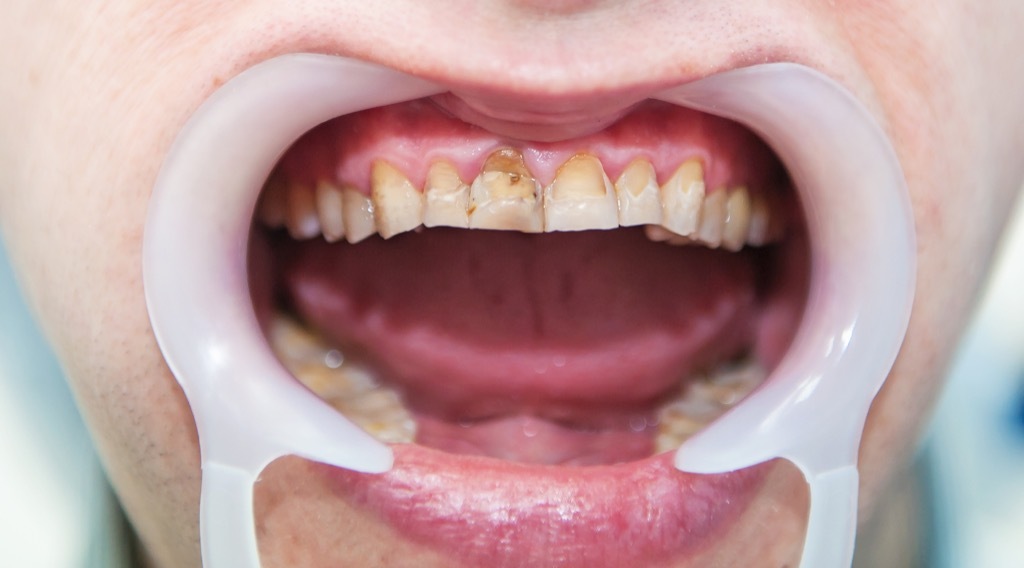

5 Amalgamfüllungen sind ungesund

Quecksilber-Amalgamkann nicht ganz sicher ist ein Stoff für Zahnfüllungen verwendet, aber sein. „Quecksilber in Zahnamalgam, eine der giftigsten Substanzen auf der Erde, ist wissenschaftlich erwiesen, jedes Mal, wenn ein Patient kaut auf einer Quecksilber-Amalgam-Füllung Blutegel“, teilt Dr. Panahpour. Zum Glück gibt es viele alternative Füllungsmaterialien auf dem Markt.